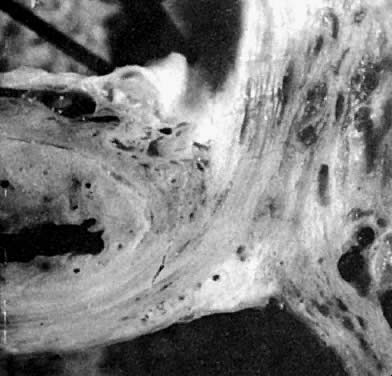

The blood vessels and lymphatics from the hypogastric plexus enter and leave the uterus and vagina along their lateral margins, as the vessels connect with their origin from the main internal iliac (hypogastric) vessels. Around these vessels are strong perivascular fibroareolar sheaths closely attached to their adventitia. The histology of these so-called ligaments has been studied repeatedly by many observers, but the findings of Range and Woodburne24 are probably the most accurate. They found that these ligaments consist principally of blood vessels (largely veins), nerves, lymphatic channels, and areolar connective tissue; the connective tissue is more dense lateral to the cervix and vagina. Collagen bundles parallel the veins, and the connective tissue contains many smooth muscle fibers associated with the adventitia of the blood vessels. They found that the loosely arranged connective-tissue mesh strands become stretched or elongated longitudinally in the direction of a force applied to them (Fig. 9).

Fig. 9. The effect of traction on the connective tissue fibers of the cardinal and uterosacral ligaments. Traction applied by forceps placed in the center of a piece of plastic net demonstrates the distortion of the pelvic tissues resulting from traction on the cervix. Condensation and obliteration of interareolar spaces account for ligaments apparent at operation, reinforced by blood vessels, lymphatics, and nerves and their sheaths, which both enter and exit along the lateral margin of the upper vagina and cervix.(Adapted from Range RL, Woodburne RT: The gross and microscopic anatomy of the transverse cervical ligament. Am J Obstet Gynecol 90:460, 1964)